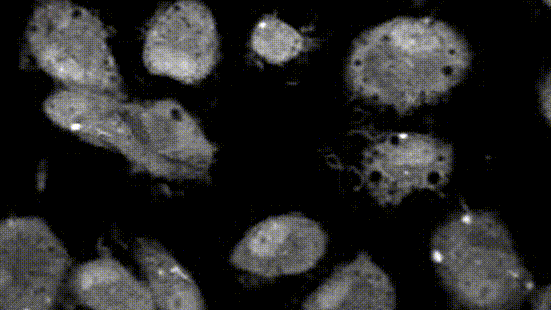

人体免疫系统宛如一场复杂而激烈的“无硝烟战争”,而“细胞焦亡”则是被外部病原体感染后的细胞主动“自爆”,同时拉响警报、召唤免疫大军的防御机制。这一重大发现,由邵峰院士团队率先揭示。

那什么是“细胞焦亡”呢?简单来说,“焦”就像火焰烧焦,焦亡是细胞死亡的一种特殊方式,它能够促进机体产生炎症,而这种炎症反应也是天然免疫反应的一种。邵峰认为,细胞焦亡是人体免疫的重要组成部分,是自然免疫系统识别外界或体内异常后产生的免疫活化机制,能在机体感染后引发炎症,并活化免疫起到保护作用。邵峰团队发现,如果能精准控制细胞焦亡,就能像“定向爆破”一样,让肿瘤细胞自我毁灭,或者让过度炎症“冷静下来”。这一发现,无疑为攻克炎症、肿瘤等疾病打开了一扇全新的大门。